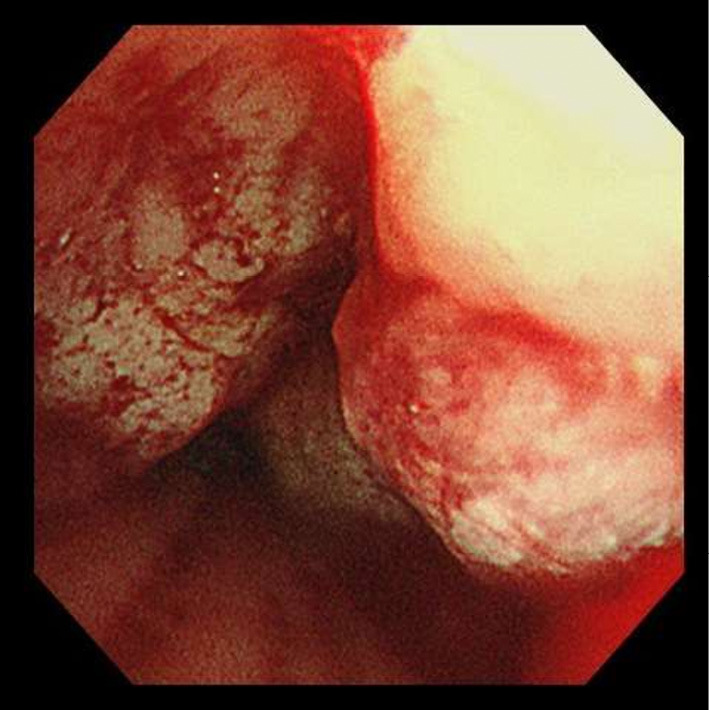

移植后淋巴细胞增生性疾病(PTLD)影响0.8-2.5%的肾移植患者,发病率在移植后1年和10-14年达到高峰。非常晚发性PTLD (VL-PTLD)可在移植后10年以上发生,据报道可达30年,但其特征尚不清楚。61岁男性,肾移植45年后出现PTLD,表现为发热、呼吸急促。计算机断层扫描显示肺和肝脏肿块,活检证实为IVB期单纯性PTLD。尽管获得了初步改善,但患者于第66天死亡。VL-PTLD可能不同于早发性或晚发性PTLD,因此需要进一步研究相关风险和管理。

Post-transplant lymphoproliferative disorder (PTLD) affects from 0.8-2.5% of kidney transplant patients, with peaks in incidence within 1 year and 10-14 years post-transplant. Very late-onset PTLD (VL-PTLD) can occur over 10 years post-transplant, reportedly up to 30 years, but its characteristics remain unclear. A 61-year-old man developed PTLD 45 years after kidney transplant, presenting with fever and shortness of breath. Computed tomography revealed lung and liver masses and biopsy-confirmed stage IVB monomorphic PTLD. Despite obtaining an initial improvement, the patient died on day 66. VL-PTLD may differ from early- or late-onset PTLD, thus necessitating further research on both the associated risks and management.